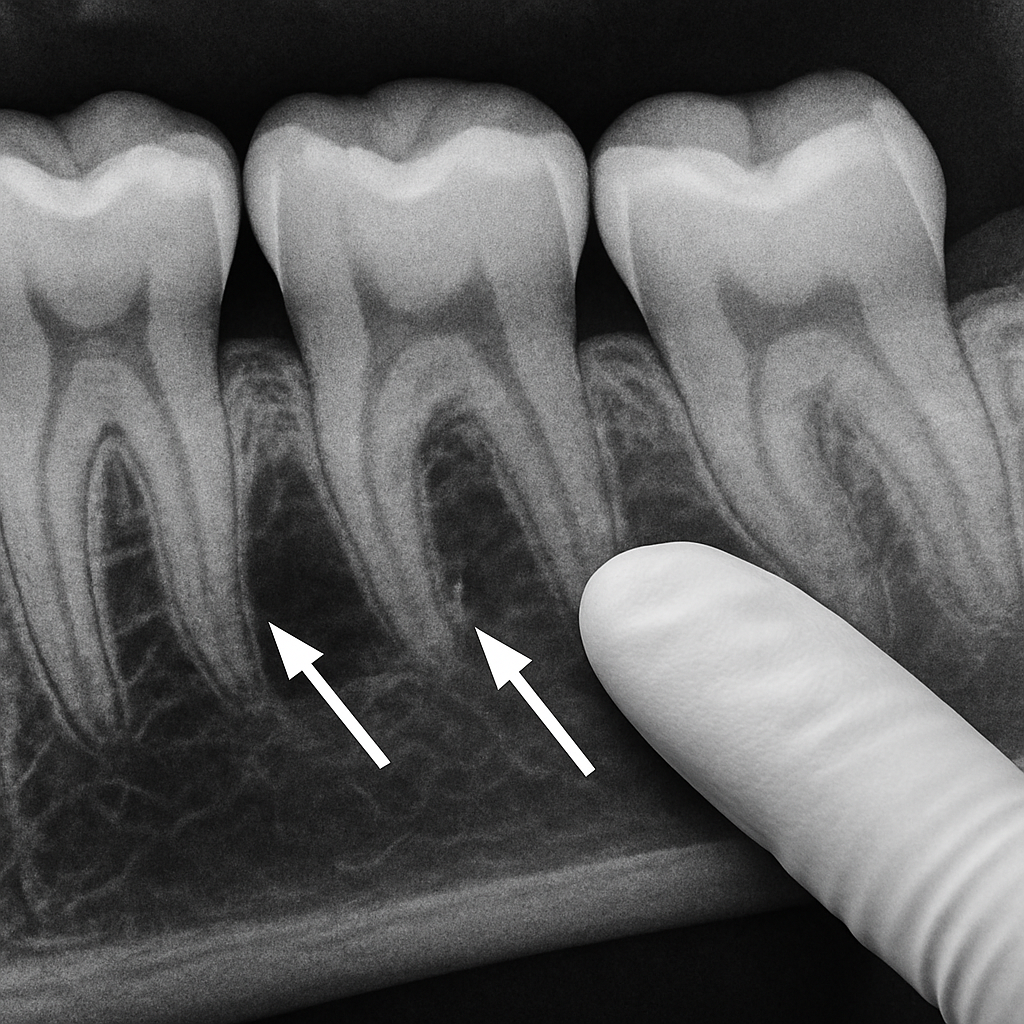

Periodontal infection begins when plaque hardens into tartar below the gumline. Bacteria trigger inflammation and pockets form between the tooth and gum. If left untreated, the body’s immune response breaks down the supporting bone — a process called bone resorption. Repeated infection and deep pockets let more bacteria survive, accelerating bone loss and making teeth unstable.

Bone grafting and guided tissue regeneration

Bone grafts and barrier membranes rebuild lost bone and support tooth stability. These procedures aim to restore the foundation around a tooth so it can be preserved rather than extracted.